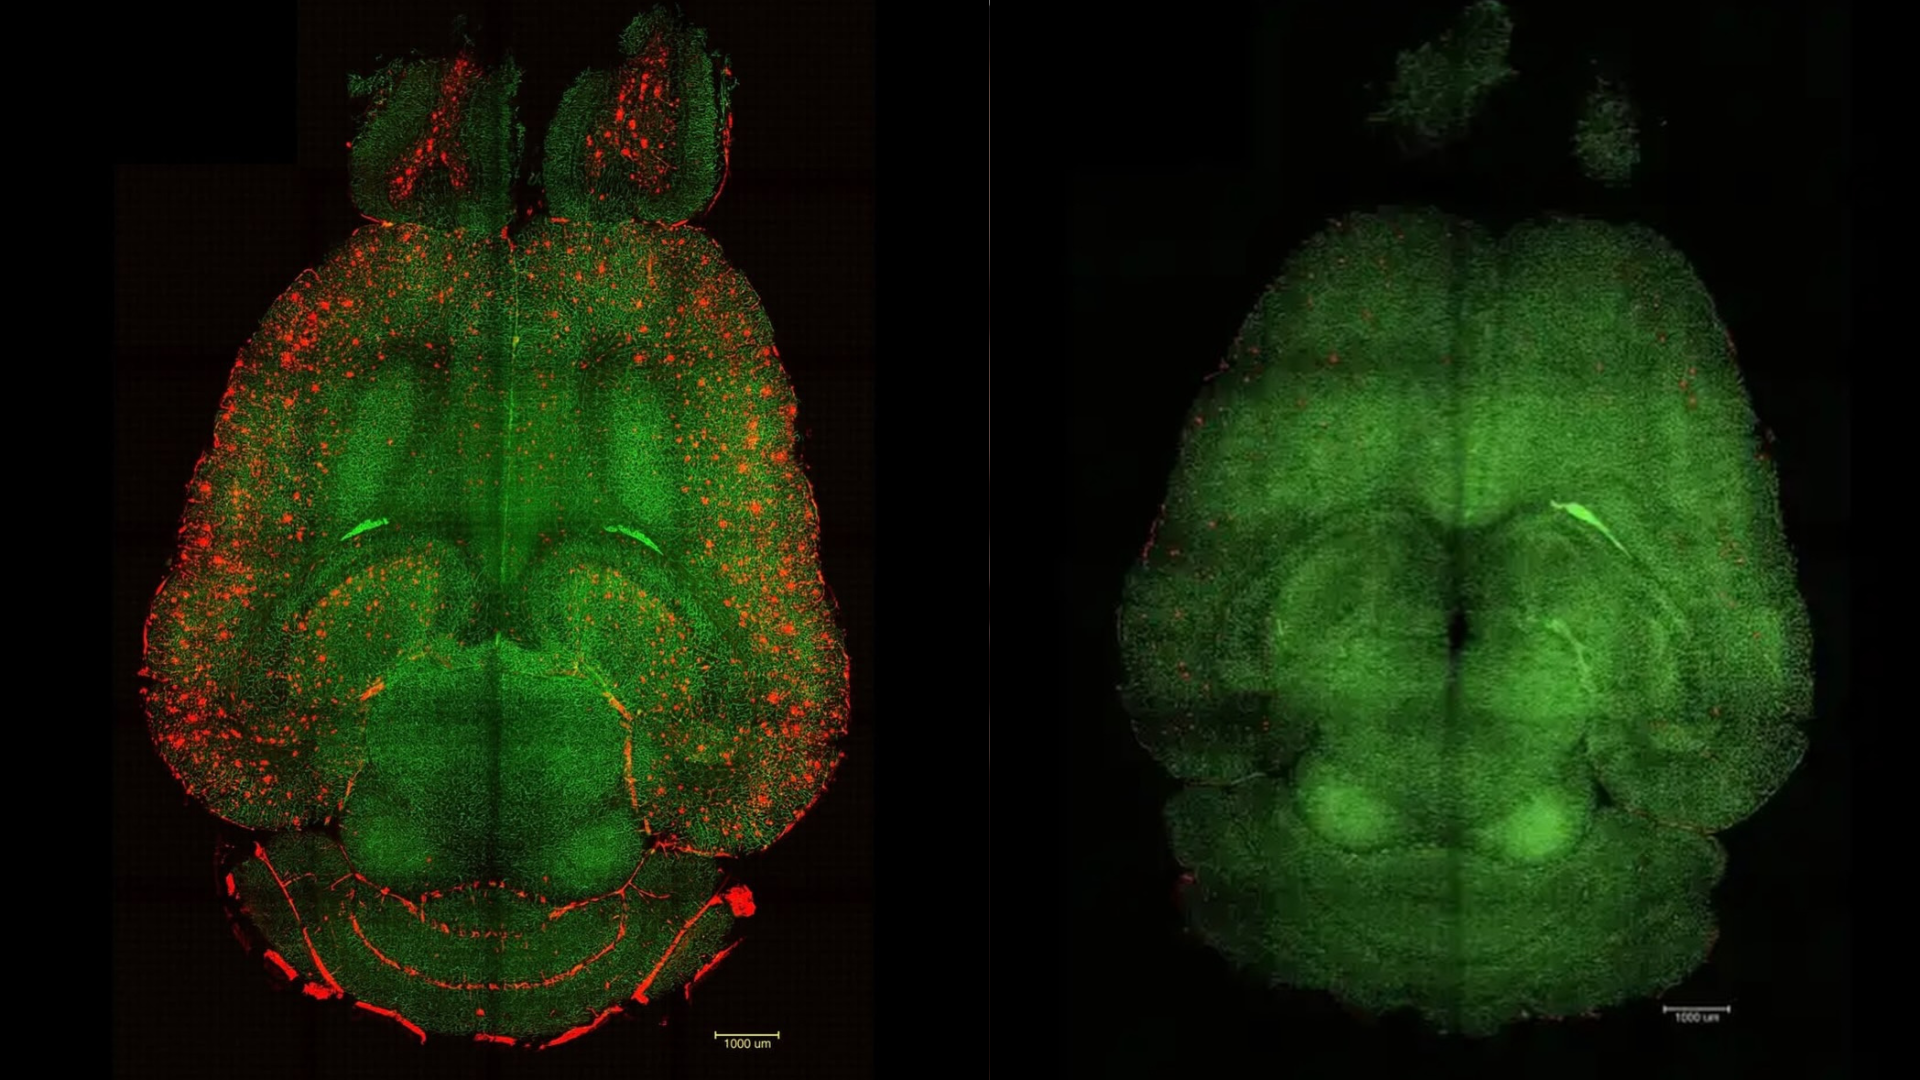

A chave do experimento está na utilização de nanopartículas desenvolvidas para atuar diretamente na barreira hematoencefálica, estrutura responsável por regular a entrada e saída de substâncias no cérebro. Quando essa barreira perde eficiência, ocorre o acúmulo de proteínas tóxicas associadas ao Alzheimer, como a amiloide-beta, que prejudicam a comunicação entre os neurônios.

Diferente das abordagens convencionais, as nanopartículas não transportam fármacos. Elas funcionam como agentes ativos que estimulam o próprio cérebro a retomar seus mecanismos de limpeza. Ao restaurar a integridade da barreira cerebral, o organismo volta a eliminar naturalmente as substâncias nocivas.

Os resultados observados em laboratório chamaram a atenção da comunidade científica. Após apenas três aplicações do tratamento, os níveis da proteína associada à doença foram reduzidos em até 60% em curto intervalo de tempo. Além disso, os animais passaram a apresentar comportamentos compatíveis com os de indivíduos saudáveis e mais jovens, indicando recuperação significativa das funções cognitivas.

A precisão do método também é apontada como um dos grandes diferenciais da pesquisa. As nanopartículas foram projetadas para interagir de forma seletiva com células cerebrais e vasos sanguíneos, interrompendo a progressão da doença ao atacar um de seus principais gatilhos: a falha na proteção cerebral.